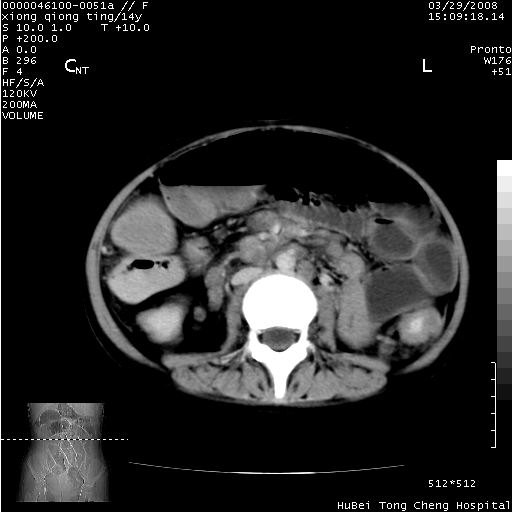

中下腹及盆腔ct轴位平扫+增强扫描(层厚10mm,螺距1.0,重建间隔10mm),图像如下:

(注:患儿检查当日上午9时口服胃肠道对比剂,下午3时许行ct扫描检查,未行对比剂直肠保留灌肠,检查当日患儿腹泻)

中下腹及盆腔ct轴位扫描(ps+ce)提示:腹部肠管明显充气扩张,并见数个不同宽度之气液平面;疑不全性肠梗阻或肠郁张。临床会诊考虑为患儿腹泻,肠郁张所致;后来未经特殊处理,患儿大便恢复正常,亦无腹胀。

临床出院诊断:1)结核性腹膜炎。2)腹膜后淋巴结结核。3)脂肪肝。